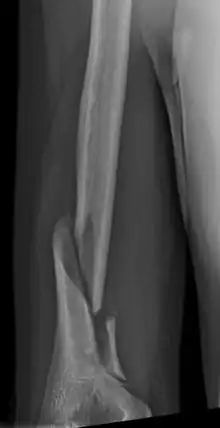

Holstein–Lewis fracture

Holstein–Lewis fracture at 5 weeks post fracture

A Holstein–Lewis fracture is a fracture of the distal third of the humerus resulting in entrapment of the radial nerve.